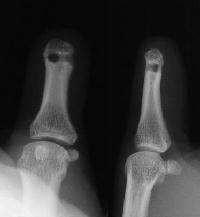

Bone tip just beneath the skin, line on the film traces the thumbnail edge.

In the amputation revision as a DIP disarticulation, the palmar digital nerves are buried in drill holes the head of the proximal phalanx to avoid sensitive neuroma symptoms.

Drill holes in the bone with protected intraosseous neuroma.